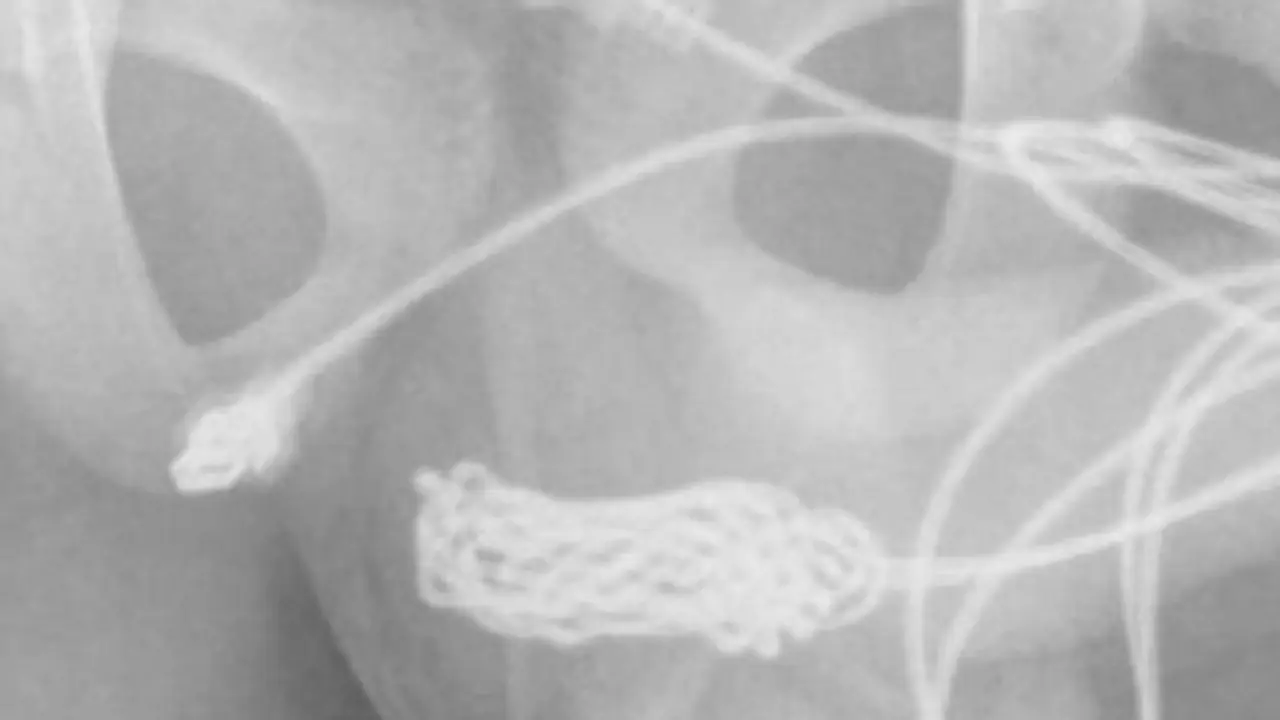

இதனால், சிறுவனின் சிறுநீரில் ரத்தமும் வரத் தொடங்கியிருக்கிறது. இதனையடுத்து, சிறுவனின் தாயார் மருத்துவரிடம் அழைத்து சென்றிருக்கிறார். அப்போது, மருத்துவமனையில் அறையில் இருந்து சிறுவனின் தயார் வெளியே சென்றதும் நடந்ததை மருத்துவர்களிடம் கூறியிருக்கிறார். யூஎஸ்பி கேபிள் இருபுற போர்ட்களும் சிறுவனின் சிறுநீர்க்குழாய் பகுதியில் நீண்டு கொண்டு இருப்பதும், ஏகப்பட்ட முடிச்சு போடப்பட் முடிச்சுகள் இருந்ததால் உலோக கம்பியை கொண்டு கேபிளை அகற்றுவது கடினமான வேலையாக இருந்ததால் அறுவை சிகிச்சை செய்ய வேண்டிய கட்டாயம் ஏற்பட்டது.

பின்னர் அறுவை சிகிச்சை மூலமே அதை வெளியே எடுக்கப்பட்டது. அப்போது தான் தெரியவந்தது அவனது ஆண் குறிக்குள் 70 செ.மீ அளவு உள்ள இருந்தது. இதனையடுத்து, மருத்துவர்களின் கண்காணிப்பில் வைக்கப்பட்டிருந்த சிறுவன் வீட்டுக்கு அனுப்பி வைக்கப்பட்டார்.